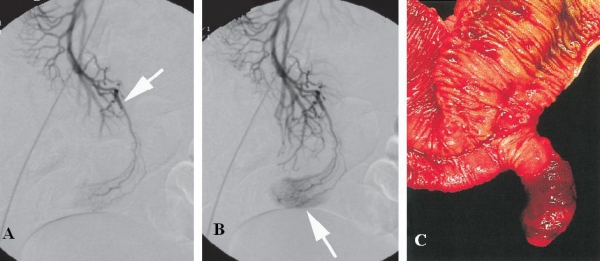

Là biến chứng thường gặp nhất ở trẻ em, chụp nhấp nháy đồ Tc-99m pertechnetate là lựa chọn tốt nhất ở trẻ em bị xuất huyết tiêu hóa nghi do túi thừa Meckel. Hình ảnh thường xuất hiện sau 30 phút sau tiêm, là những vùng tập trung thuốc tròn nhỏ ở ¼ bụng dưới phải. Trên CT túi thừa đang xuất huyết có thể thấy thoát thuốc cản quang vào lòng ruột non, trong túi thừa. Nguyên nhân thường do loét vì hay chứa mô tuyến dạ dày, tụy lạc chỗ tiết acid gây loét vào mạch máu nuôi túi thừa.

Hình 12: A, CT cản quang thì động mạch, hình ảnh thoát thuốc cản quang từ cổ túi thừa Meckel ở đoạn xa hồi tràng (mũi tên). B, Thì trễ, hình ảnh tăng đậm độ và lẫn thuốc cản quang trong lòng túi thừa do xuất huyết ( mũi tên).

( Danzer, P. Gervaz, A. Platon, P.-A. Poletti (2003). Bleeding Meckel’s diverticulum diagnosis: an unusual indication for computed tomography. Abdominal Imaging 28:632)

Hình 13: Xuất huyết tiêu hóa do niêm mạc dạ dày lạc chỗ trong túi thừa Meckel ở bệnh nhân nam 22 tuổi. A, CT không cản quang. B, thuốc cản quang thoát vào lòng túi thừa Meckel (Alexandra Platon, Pascal Gervaz et al (2010). Computed tomography of complicated Meckel’s diverticulum in adults: a pictorial review. Insights Imaging 1:59)